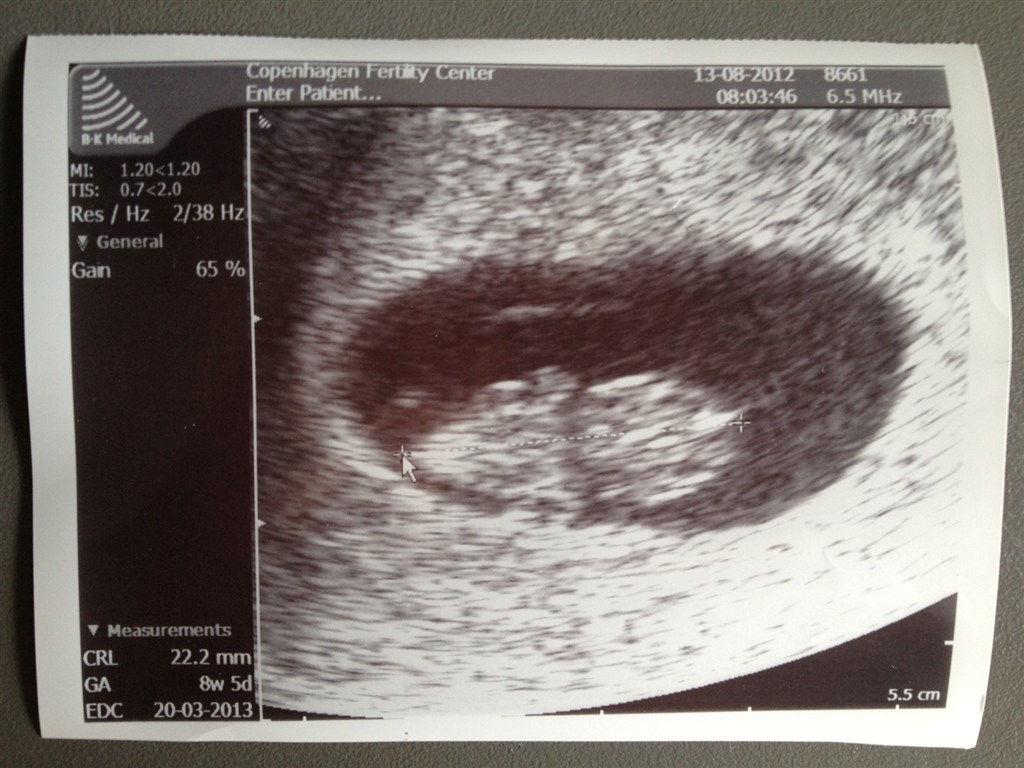

Så var vi til den første scanning og alt er som det skal være

Jeg har termin ca 20. marts